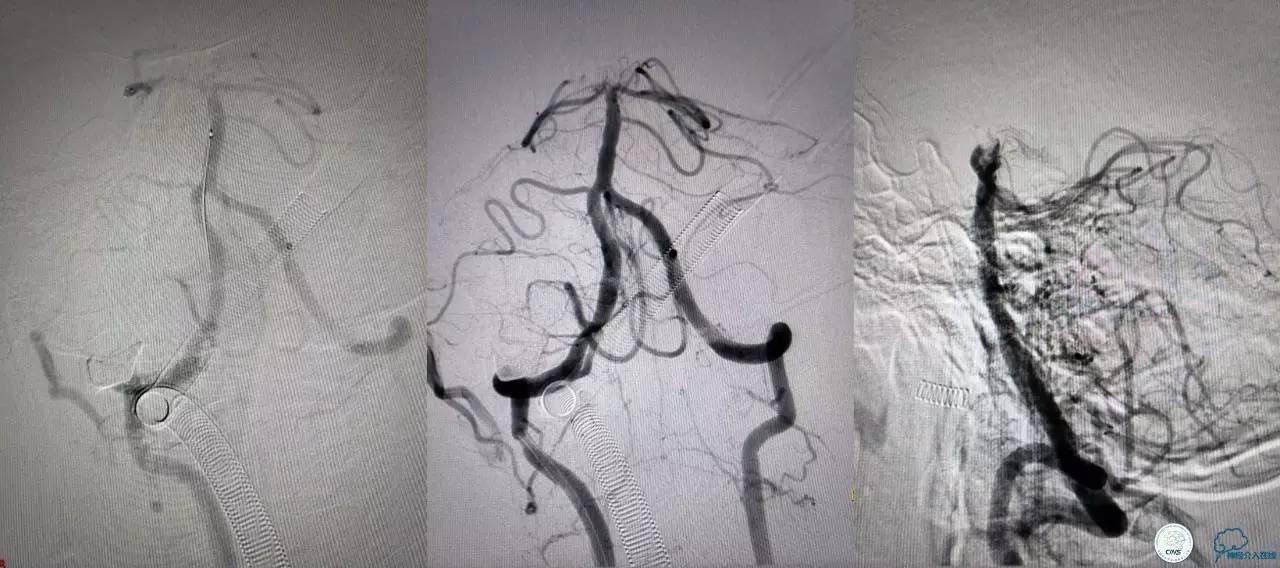

第三次取栓,支架放入左侧大脑后取栓。

第三次取栓后,左侧大脑后动脉开通,但是栓子再次栓塞右侧大脑后动脉,血栓在基地动脉顶端来回左右摆动,下一次,怎办?血栓负荷太多,可以使用solumbar技术,可以没有颅内导管,没办法,换用更大的支架6-20mm,但费用增加不少,与家属沟通后同意使用,第四次取栓:

血栓负荷还是很大,左侧大脑后再通,但右侧大脑后又闭塞,只能第五次取栓,支架放到右侧大脑后动脉更远。

好大的血栓,支架释放后,血管无复流,拉一把!

没错,没看错!血管成功实现再通,术中取栓的栓子如下。

术后生命体征平稳,成功撤呼吸机,肌力较前好转,复查头颅CT:

右侧丘脑高密度影,右侧枕叶可能也有梗死,祈祷慢慢恢复吧!